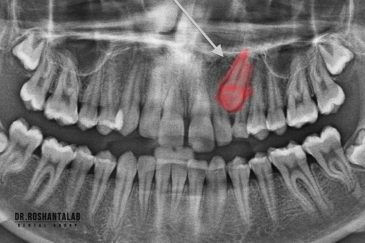

🔸 کاشت ایمپلنت دندان بدون درد

🔸کاشت ایمپلنت فلپ لس یا بدون جراحی و بدون بخیه زیر سه دقیقه

🔸 کاشت دندان یک روزه ( کشیدن و کاشت همزمان )

🔸 ایمپلنت دیجیتال و ساخت روکش دیجیتال

🔸جراحی پیشرفته نظیر سینوس لیفت